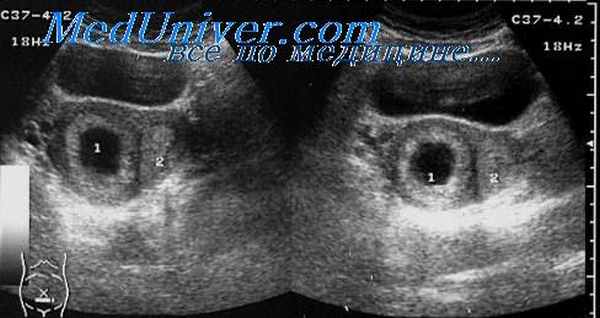

Часто помимо анализов крови, особенно если результаты сомнительные, могут назначить УЗИ. На ранних сроках плод может быть плохо видно, и женщине приходится ждать 1‒2 недели, чтобы эмбрион начал визуализироваться при ультразвуковой диагностике. При подозрении на патологии беременную могут положить в стационар для наблюдения и возможности принять экстренные меры.

Контроль за уровнем хорионического гонадотропина человека помогает своевременно определить неправильное прикрепление эмбриона - внематочную беременность, УЗИ подтвердит или опровергнет диагноз. ХГЧ при внематочной беременности характеризуется тем, что отсутствует динамика роста хорионического гонадотропина человека, в отличие от роста гормона во время нормальной беременности. Следует не забывать, что снижение уровня гормона ХГЧ - не всегда показатель только внематочной беременности – его снижение происходит при других патологических состояниях плода, плаценты.

Если даже УЗИ в сочетании с анализами крови не могут достоверно показать наличие или отсутствие внематочной беременности специалист может прибегнуть к диагностической лапароскопии. Она представляет собой процедуру, при которой врач операбельным путем осматривает область малого таза пациентки. В случае если диагноз подтвердился на раннем сроке неправильно закрепившийся плод удаляется.